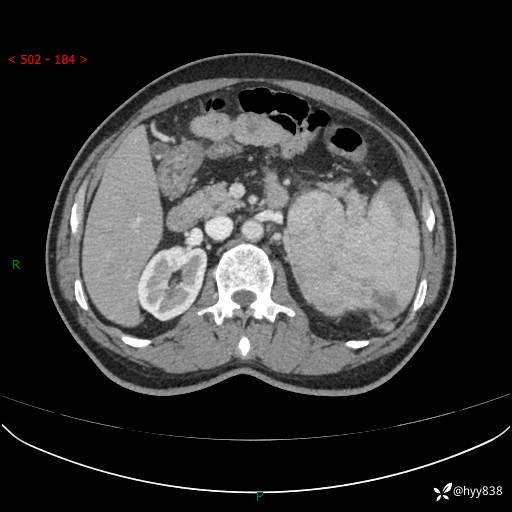

上腹部CT平扫

增强(动脉期+静脉期)